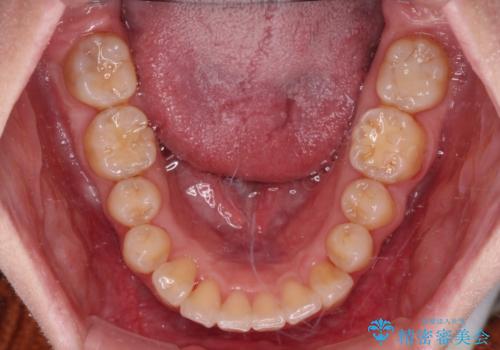

カリエール・ディスタライザーを用いたことで上顎前歯の突出感はスムーズに解消され、歯列不正は1年半ほどでほぼ改善することができました。

しかし、その後インビザライン特有の奥歯がうまく噛めないという問題が長引き、改善に1年近い期間を要することとなりました。